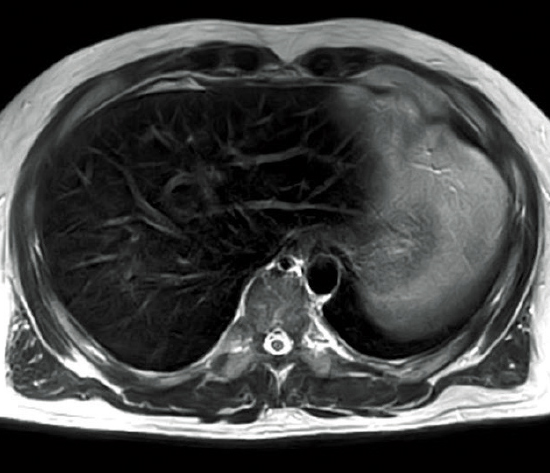

Based on our proprietary technology, this system has opened up the potential for 1.5T systems, providing superb image quality and superior install flexibility inherited from permanent-magnet MRI systems.

Smart QUALITY